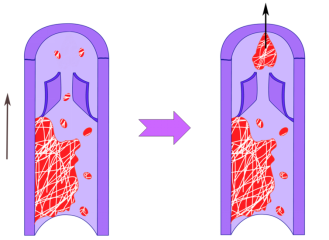

二、血液为什么会结块

血液在血管内不停流动,为什么会凝固成栓呢?血栓的形成是多种因素作用的结果,国外专家归纳了一下,主要有三方面因素(图3),第一个是血管内膜的损伤,第二个是血液的高凝状态,第三个是血液的流速变慢。这三个原因相辅相成,共同形成血栓。

图3 血栓形成三因素

上面三个因素,说起来简单,理解起来可能有点困难。什么是血管内膜的损伤?什么又是血液的髙凝状态呢?打个比方吧,血管就好比是下水道,如果管道内壁很光滑,冲下去的水流很快,并且水很淸,那这个下水道就不容易堵塞。但是如果情况恰恰相反呢,下水道坑坑洼洼,水流很慢,我们还往里面倒点稀饭,掺点垃圾,那这个下水道不堵塞才怪。同样的道理,如果血管和血液也出现了这种情况,也就容易堵塞,导致血管内血栓的形成。